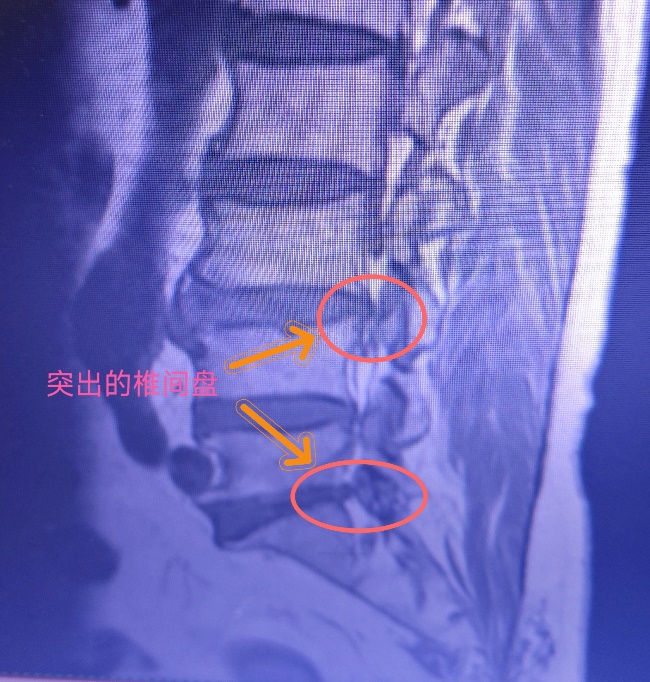

丰顺县人民医院麻醉疼痛诊疗中心2023年7月份引进德国进口临床臭氧治疗仪至今,已常规开展腰椎间盘臭氧消融术数十例,凭借一根“细针”,在C臂X光机的指引下,将适量的臭氧气体注射到病变椎间盘髓核,达到消融固缩突出椎间盘,解除脊神经压迫疼痛的治疗效果,操作快速简便,微创且恢复快,凭借出色的疗效,深受广大患者好评!

在影像的引导下,通过穿刺针将合适浓度、剂量的臭氧(O₃)和药物注入到变性突出的椎间盘内外,利用臭氧的消炎、镇痛等功能,消除椎间盘内外致痛因素,并可逐渐解除椎间盘对神经的压迫。

单纯椎间盘源性疼痛,即由椎间盘膨出、突出、脱出所引起的疼痛。